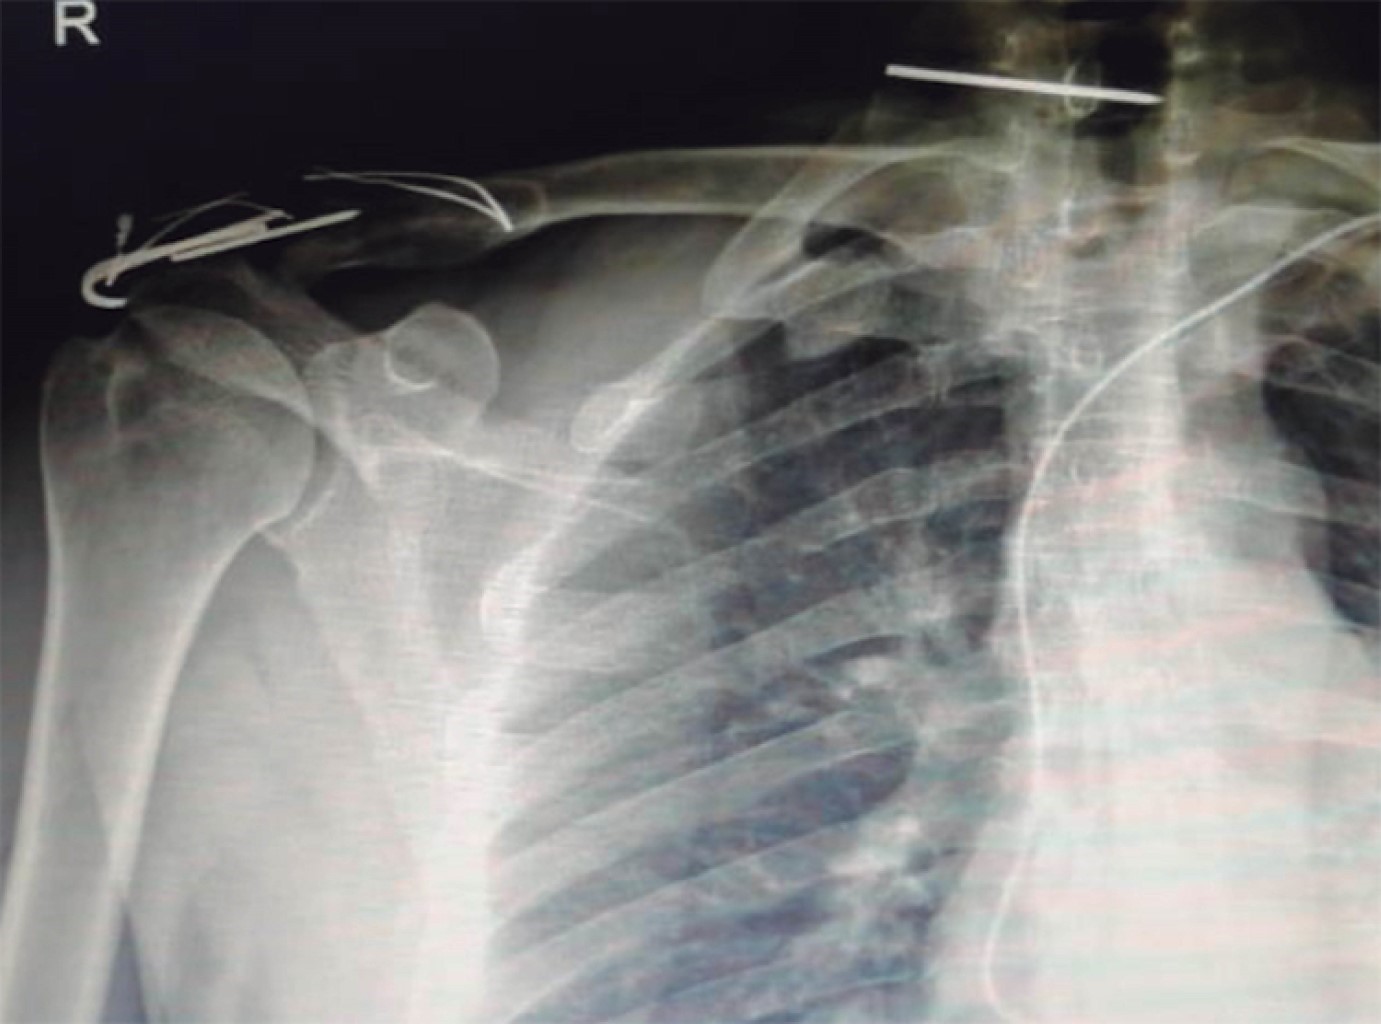

Paciente masculino de 32 años de edad que sufre accidente laboral, herida con objeto cortopunzante (fragmento de varilla metálica) a nivel cervical posterior. Es valorado en sala de emergencias de hospital privado en donde indican manejo conservador; sin embargo, dos semanas después presenta cervicalgia izquierda con irradiación a hombro ipsilateral, parestesias y sensación de disminución de fuerza, por lo que decide acudir a valoración con especialista en columna. Al momento de la valoración actualmente reportada, se presenta con rangos de movilidad de columna cervical conservados. Dolor rotación izquierda, se evidencia cicatriz de aproximadamente 1 cm de longitud a nivel de borde posterior de músculo esternocleidomastoideo, no se palpa masa, dolor moderado a la palpación profunda, sprue izquierdo positivos dermatomas C5-C6. Rangos de movilidad de miembro superior izquierdo: flexión 140° dolorosa, extensión −10°, abducción 120° dolorosa (Figura 5). Neurológico: sensibilidad 2/2, Daniels 5/5 en las cuatro extremidades.

En radiografía anteroposterior cervicotorácica se evidencia cuerpo extraño metálico a nivel C6-C7 izquierdo (Figura 6). En imágenes tomográficas se observa cuerpo extraño metálico a nivel de apófisis transversa izquierda de C7 (Figura 7). Se realiza angiotomografía en la que se evidencia proximidad de cuerpo extraño a grandes vasos, con integridad de los mismos (Figura 8). Se realizó abordaje cervical anterolateral izquierdo a través de plexo cervicobraquial y disección neurovascular; con ayuda de intensificador de imágenes, se localizó el cuerpo extraño en apófisis transversa de C7 izquierda, con posterior extracción sin complicaciones (Figura 9). El paciente evolucionó favorablemente sin déficit neurológico; como protocolo se indicó antibioticoterapia por tratarse de cuerpo extraño.